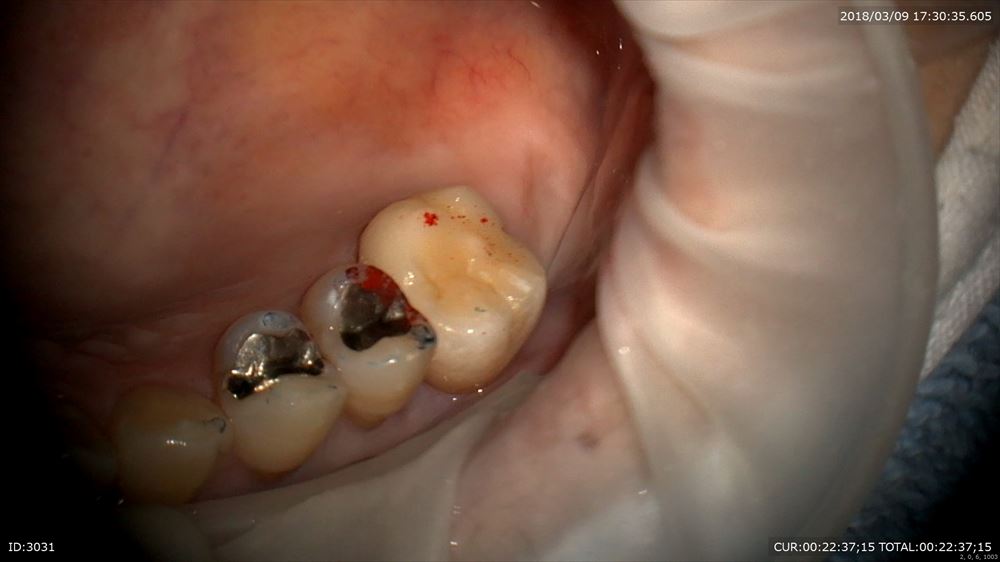

今日最後の患者さまは奥歯のセラミックのセット。

歯型模型

綺麗。